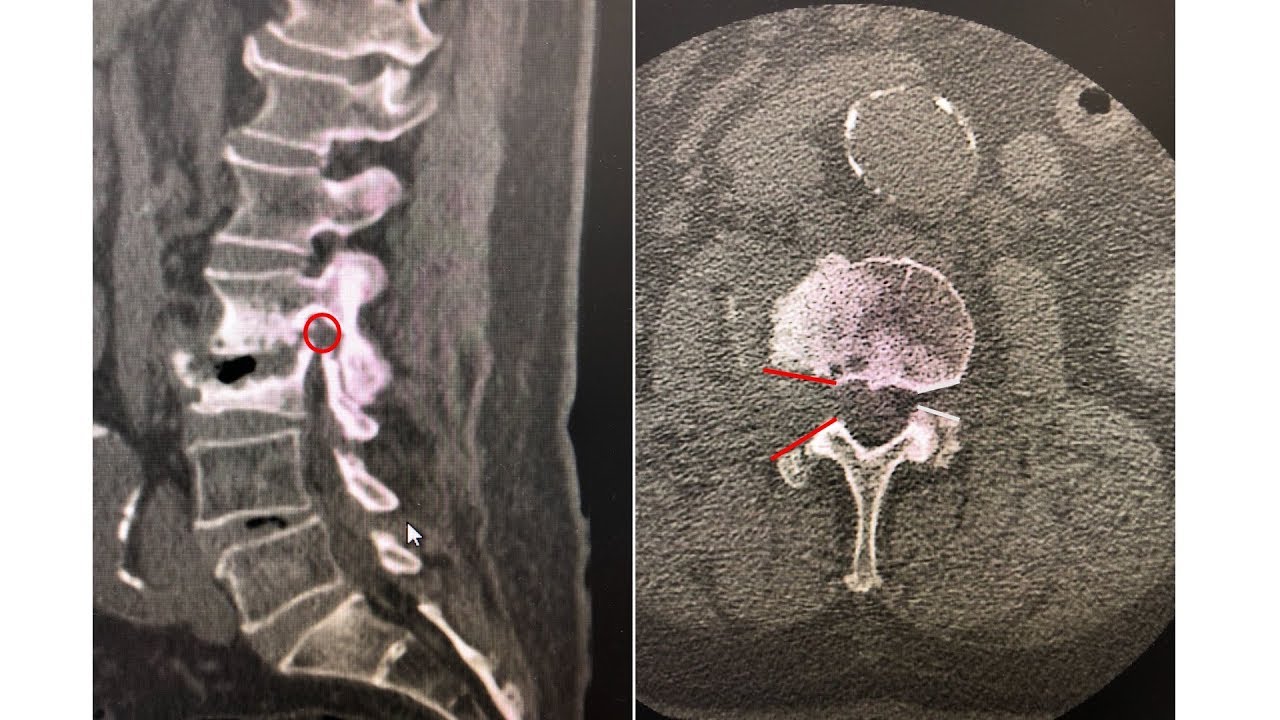

Cirurgia endoscópica da coluna vertebral

A cirurgia endoscópica de coluna possibilita, hoje, o tratamento cirúrgico da hérnia de disco por vídeo, sob anestesia local e com mínima invasão, sem a necessidade do uso de implantes, como parafusos e pinos, e sem a necessidade de cirurgia aberta. Desta forma, a recuperação é mais rápida, com menos dor, voltando para casa horas após o procedimento, e retornando às atividades de trabalho em poucos dias.

Os discos intervertebrais separam cada uma das vértebras da coluna, permitindo o movimento e conferindo estabilidade entre elas. O disco é formado por um anel fibroso e um núcleo de tecido mais mole. Quando há uma degeneração do disco, o anel fibroso pode romper, havendo extravasamento do material interno do disco. Esse processo configura a hérnia discal. A dor lombar provém do desgaste e instabilidade. E quando esse fragmento herniado comprime os nervos que passam logo atrás dos discos, pode haver dor irradiada para o membro correspondente, bem como dormência, formigamento, queimação ou outros sintomas neurológicos. Na maioria das vezes, o tratamento da hérnia de disco pode ser conservador.